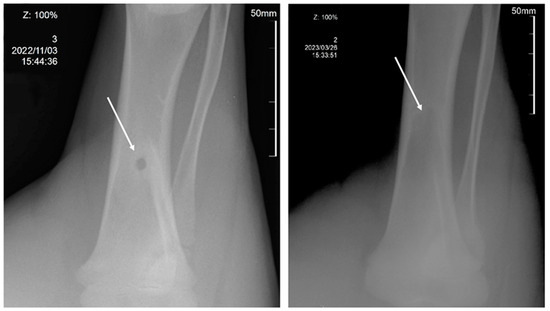

2.5. In Vivo Assays of 3D Scaffolds